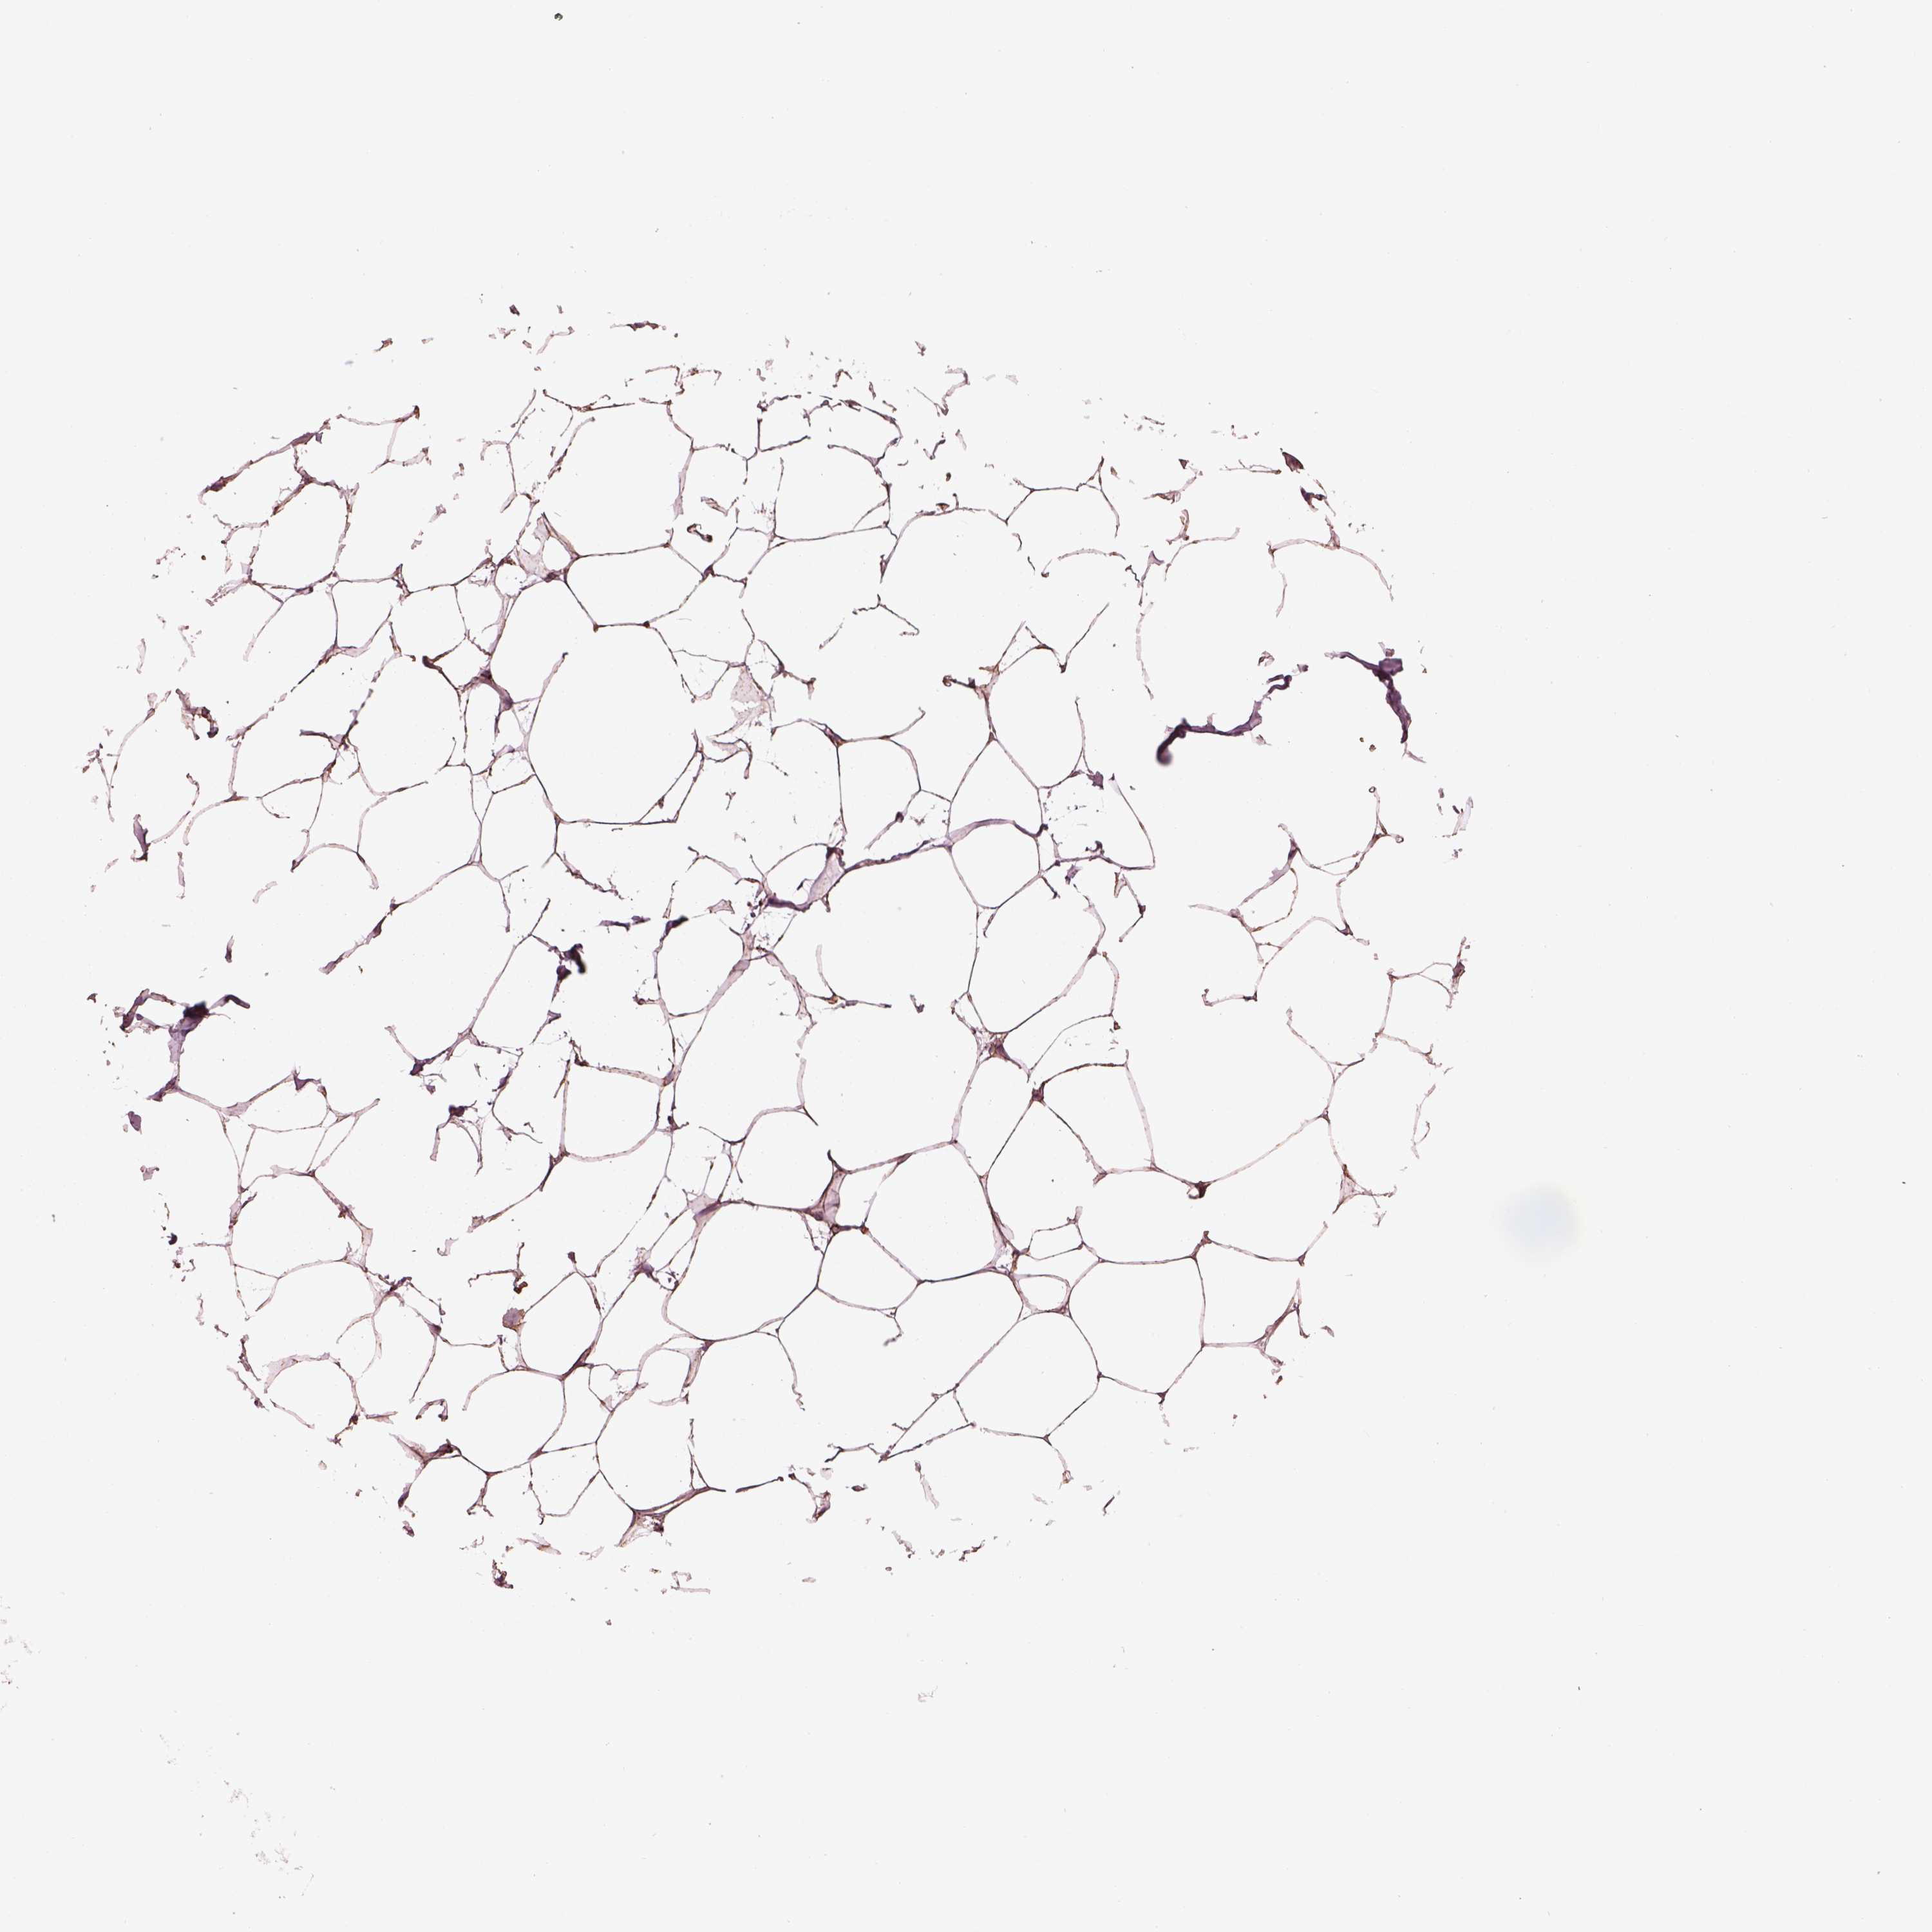

BREAST - Antibody stainingi

Antibody staining in the annotated cell types in the current human tissue is reported as not detected, low, medium, or high, based on conventional immunohistochemistry profiling in selected tissues. This score is based on the combination of the staining intensity and fraction of stained cells.

Each image is clickable and will lead to virtual microscopy that enables deeper exploration of all samples and also displays staining intensity scores, fraction scores and subcellular localization as well as patient and tissue information for each sample.

Antibody HPA072613

Adipocytes Medium

Glandular cells High

Myoepithelial cells Not detected